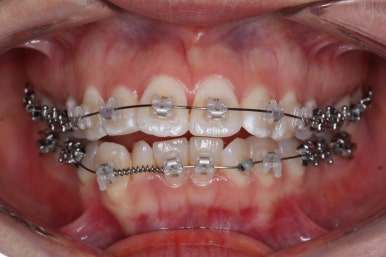

틈은 다 다물어졌고, 부가적인 정교한 마무리 과정을 더 거치게 됩니다.

중앙선도 잘 맞고 교합도 잘 마무리되었습니다.

이 뽑은 자리가 다시 벌어지지 않게 앞니가 다시 틀어지지 않게 유지철사를 부착하고 마무리를 하였습니다.

전후 비교해 보겠습니다.

중앙선, 교합, 뻐드러짐 모두 좋아졌고 이를 뽑고 교정했지만 발치 공간이 남지 않고 잘 마무리 되었습니다.